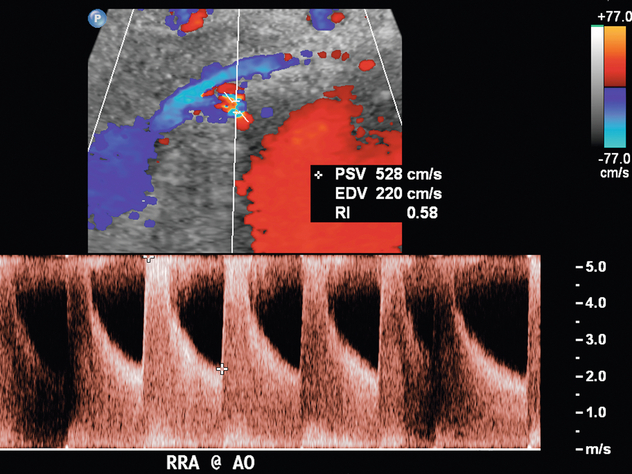

Артериовенозная фистула в нативной почке встречается редко, за исключением случаев предшествующей биопсии почки, и ее нельзя заподозрить при сонографии, если не проводится цветная или энергетическая допплерография. Цветной или энергетический допплер обычно показывает большое извилистое скопление сосудов. Спектральные допплеровские сигналы почечных артерий, питающих фистулу, покажут высокую скорость и низкое сопротивление ( рис. 9-19 ). Основная почечная вена может быть расширена, а в венах вблизи фистулы могут обнаруживаться артериализованные волны ( рис. 9-20 ).

Для прямой спектральной допплеровской диагностики РАС были предложены различные критерии, что вызвало разногласия. PSV более 200 см/с ( рис. 9-12 ) был предложен для допплеровской диагностики уменьшения диаметра почечной артерии на 60%. В недавнем метаанализе PSV был лучшим критическим фактором в диагностике РАС с чувствительностью и специфичностью 85% и 92% соответственно. 29 Соотношение PSV почечной артерии и PSV аорты (RA/Ao) является еще одним критерием, предлагаемым для диагностики РАС. Соотношение RA/Ao PSV более 3,5:1 ( рис. 9-13 ) предполагает значительный уровень РАС, обеспечивая чувствительность 91% и специфичность 91%. Повышенное соотношение пиковой систолической скорости почечной артерии к систолической скорости дистальных почечных артерий также было предложено в качестве критерия диагностики РАС. Одно исследование 187 почечных артерий с ангиографической корреляцией также показало, что абсолютная почечная междолевая скорость PSV менее 15 см/с приводила к чувствительности и специфичности 87% и 91% соответственно для допплеровской диагностики 50% стеноза.Цзянь-Чу и др. недавно изучили влияние атеросклероза и возраста на параметры допплерографии для диагностики РАС и предполагают, что использование диагностических порогов почечно-аортального соотношения и почечно-междолевого соотношения различается у пациентов старше и моложе 46 лет. На другие сонографические критерии в их исследовании возраст пациентов существенно не влиял.